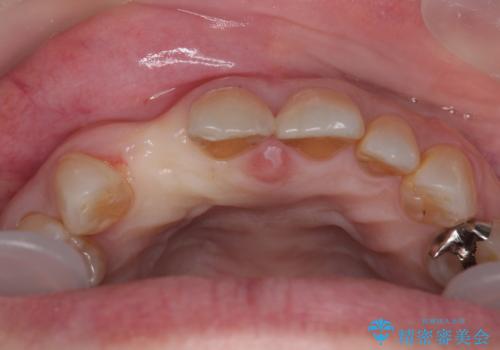

仮歯を事前に用意し、インプラント埋入時に即日で仮歯を装着する、即時荷重インプラントの計画で治療を進めて行くこととしました。

新幹線や飛行機を利用しても来院であり、極力来院回数を減らしたり、東京に用事があるタイミングに合わせてアポイントを調整したりと、負担が少なくなるようにして治療を進めて行きました。

来院間隔があいたため、予定よりも長くなりましたが、大きなトラブルもなく、外科処置は1回のみ、最小の来院数で無事に治療を終えることができました。